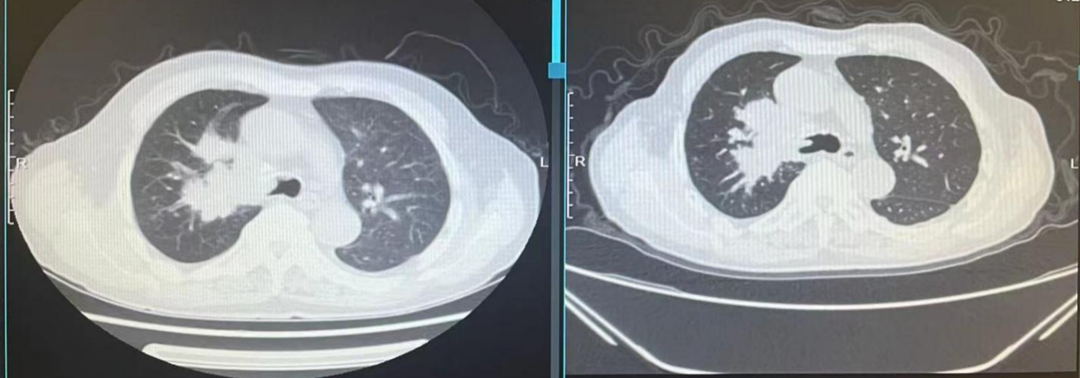

图22、呋喹替尼治疗期间,患者肺部转移灶胸部增强CT评估情况:左(2020-10-23)、中(2021-05-27)、右(2021-07-06)

图23、呋喹替尼治疗期间,患者口腔颊黏膜转移灶口腔增强CT评估情况:左(2020-10-23)、中(2021-05-27)、右(2021-07-08)

疾病进展:2021年8月,患者出现咳胸闷,咳嗽。胸部CT提示双肺转移瘤相仿,右侧支气管内多发软组织密度影。

图24、胸部增强CT显示支气管内新增转移病灶:左(2021-07-06)、右(2021-08-31)